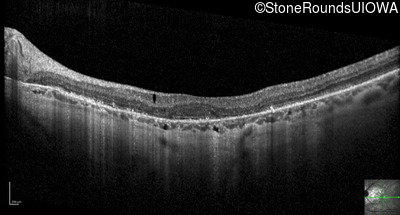

Optical Coherence Tomography - Right - 20/25 +1

Exemplar / OCT Stack

OCT Stack

Optical Coherence Tomography - Left - 20/25 +3